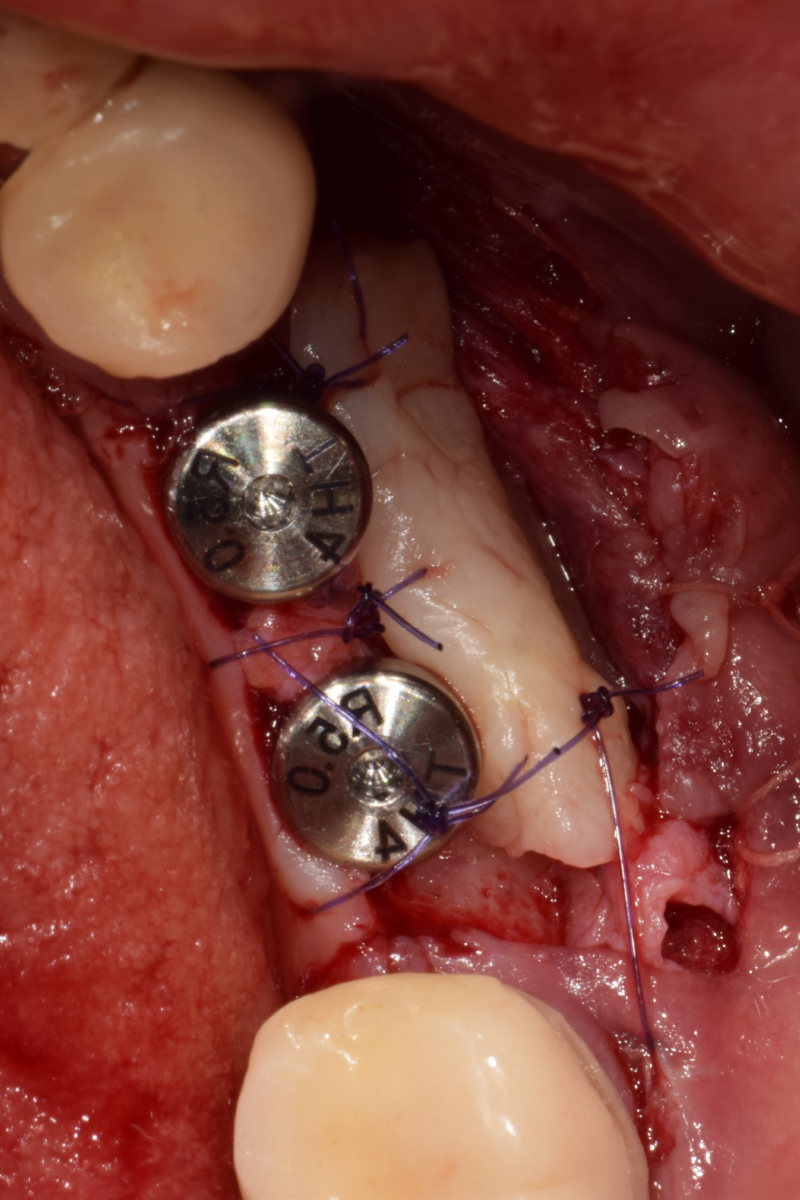

즉시 식립 임플란트 전후 사례

• 식립 전

식립 후